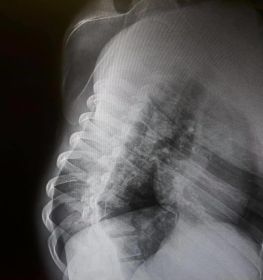

Omurga eğriliği yaşan insanlarda eğer eğrilik 40 dereceyi aşmış ise cerrahi operasyon ile tadavi edilir. Bu şekilde bir tedavi çok riskli ve zordur. Ardından ise mutlaka fizik tedavi ek olarak da korse tedavisi uygulanmalıdır.